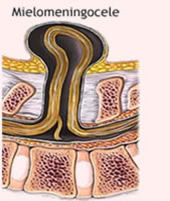

MIELOMENINGOCELE

También conocido como espina bífida abierta, el mielomeningocele es la forma de espina bífida más grave y la forma a la que las personas se refieren, por lo general, cuando usan el término espina bífida.

En el caso del mielomeningocele, el conducto vertebral del bebé queda abierto en varias vértebras de la parte inferior o media de la espalda. Debido a esta abertura, tanto las membranas que protegen la médula como la misma médula espinal sobresalen en el nacimiento y forman un saco en la espalda del bebé y son claramente visibles.

En algunos casos, la piel recubre el saco. Sin embargo, por lo general, los tejidos y los nervios quedan expuestos, lo que aumenta las probabilidades de que el bebé tenga infecciones que pongan en riesgo su vida.

La médula espinal puede estar dañada o no bien desarrollada. Su localización más frecuente es la región lumbar o lumbosacra.